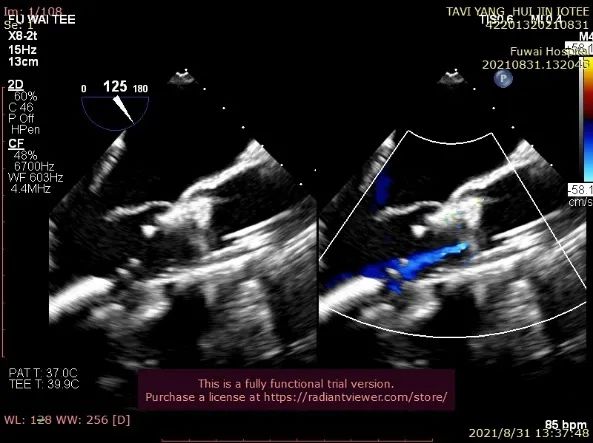

TA-TAVR在全麻和气管插管下进行。经右侧股静脉置入临时起搏器,经右侧股动脉在患者主动脉无冠窦内放置1根6F猪尾导管进行协助定位(图1)。

图1. TEE和放射线显示猪尾导管、临时起搏导线、导丝

透视下定位后第五肋间小切口进胸,打开心包,选择心尖裸区缝制六边形荷包。心尖穿刺后将泥鳅导丝过主动脉瓣经升主动脉、主动脉弓到达降主动脉膈肌水平,通过TEE确认细导丝没有与二尖瓣腱索缠绕(图2)。

图2. TEE和放射线显示输送器进入升主动脉根部、瓣环平面以上水平